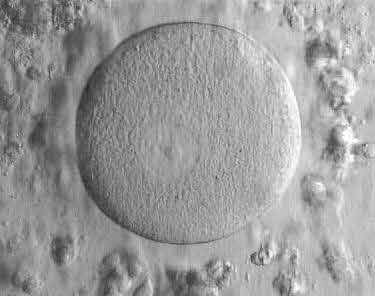

I am a scientist at the University of Manchester and I work several different projects. I am trying new and exciting ways to create Human Embryonic Stem Cells from human eggs (oocytes) that could

possibly be used to help treat diseases like Parkinson’s and diabetes, as well as helping patients with spinal cord injuries (like Superman). As well as this, I look inside very early embryos to see different genes that control their growth and development